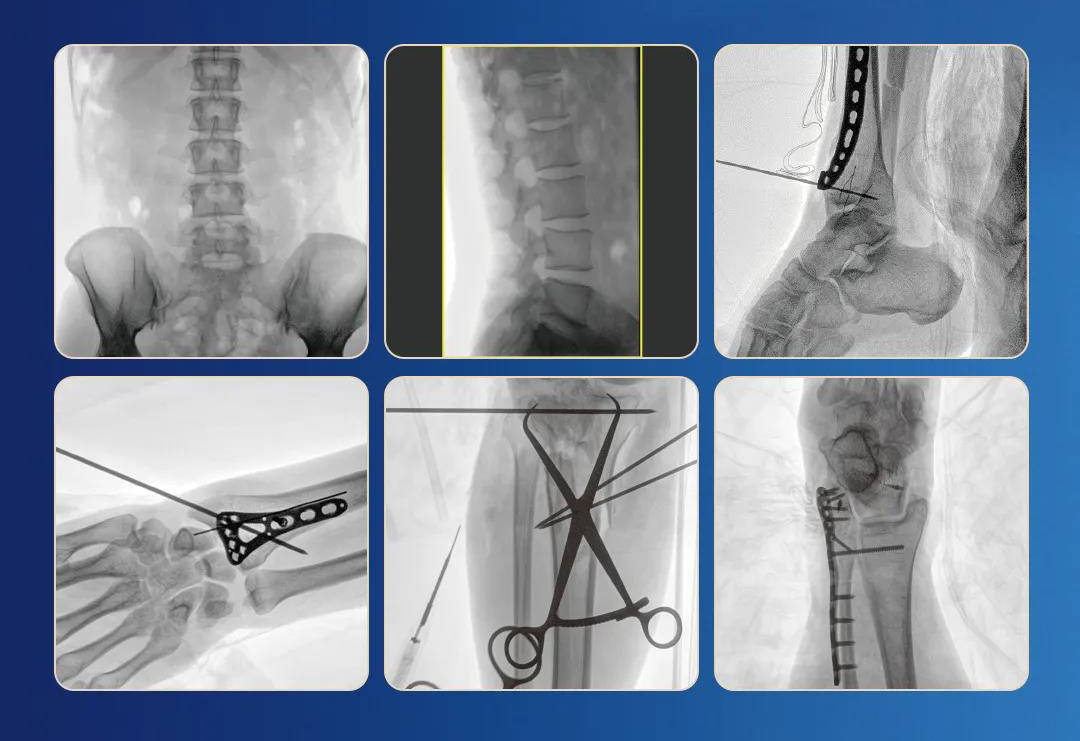

一、臨床應(yīng)用

1.關(guān)節(jié)手術(shù)

2.創(chuàng)傷手術(shù)

3.脊柱手術(shù)

4.疼痛治療

2.圖像清晰細(xì)膩

清晰的像素,低信噪比,細(xì)小的組織結(jié)構(gòu)也可以清晰顯示。